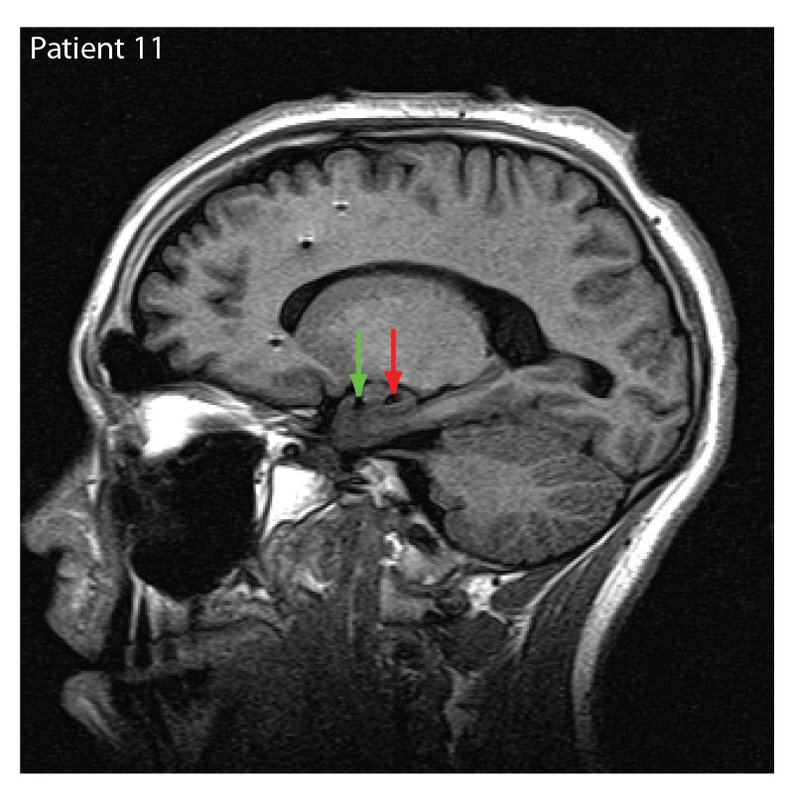

Evaluating another person's emotions based on facial expressions can sometimes be a complex task. As it turns out, this process isn't so easy for the brain to sort out either. Building on previous studies targeting the amygdala, a region in the brain known to be important for the processing of emotional reactions, a team of researchers from Caltech, Cedars-Sinai Medical Center, and Huntington Memorial Hospital in Pasadena, have found that some brain cells recognize emotions based on the viewer's preconceptions rather than the true emotion being expressed. In other words, it's possible for the brain to be biased. The team was able to record these responses from single neurons using existing electrodes—indicated by the arrows in the MRI image at right—placed in the brains of patients who were being treated for epilepsy. Participants were shown images of partially obscured faces showing either happiness or fear (see secondary image) and were asked to guess the emotion being shown. According to the researchers, the brain responded similarly whether or not the patient guessed the correct emotion.